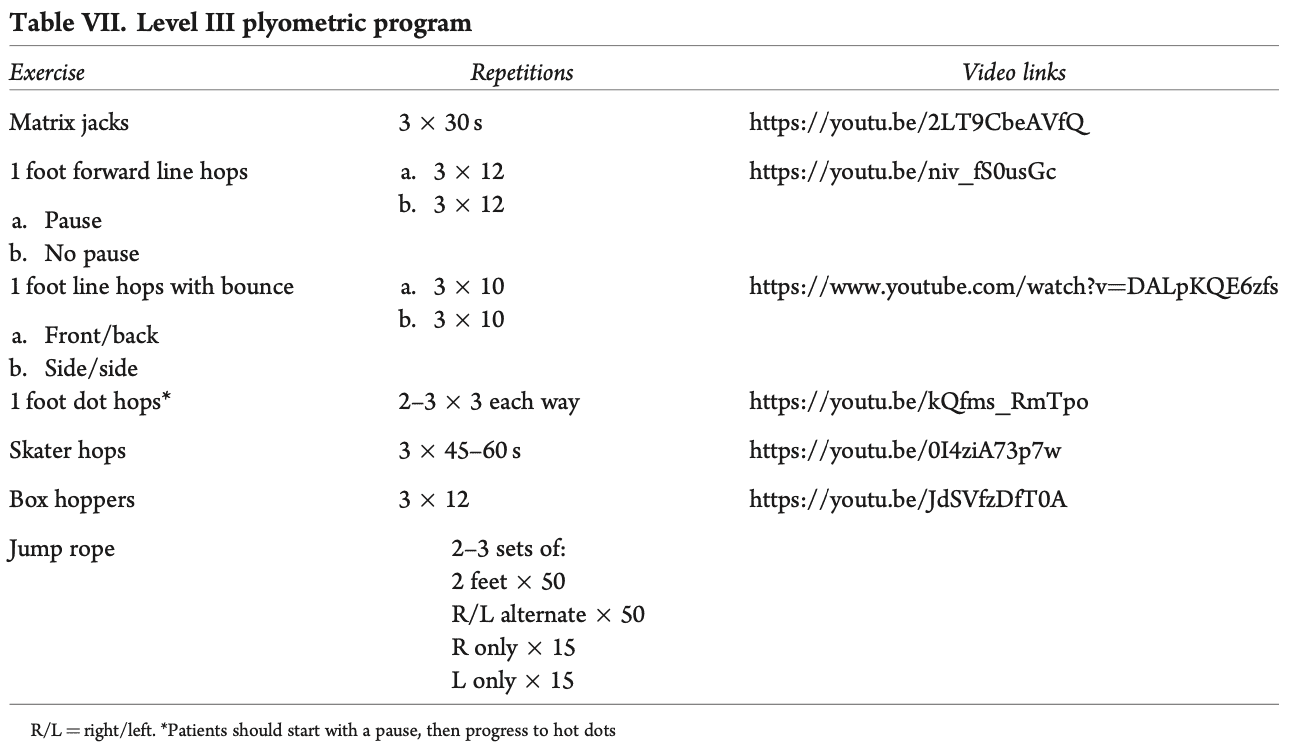

- Фаза 2 беше бърза реакция и плиометрична дейност. В тях се посочва следното: "Бързата мускулна реакция и плиометрията започват в тази фаза, като се стига до около 500-600 контакта между единия и двата крака. Така, ако средният оборот на бегача е 170-180 крачки в минута, за да достигне необходимите 500-600 контакта с един крак, ще е необходимо да бяга 5-7 минути."

Преминаването към програмата за ходене/бягане е разрешено, когато участниците са завършили успешно фаза 1 и плиометричната програма от ниво I на фаза 2, могат да ходят без да куцат и нямат болка при ежедневните дейности. И тук съветът беше тази програма да се започне на бягаща пътека. Трябваше да се спазват следните правила: (i) без хълмове и наклони, (ii) без работа за скорост, (iii) работа върху формата и (iv) бягане всеки втори ден. В идеалния случай те трябва да продължат плиометричната програма от II и III ниво.